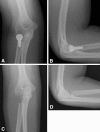

Figures